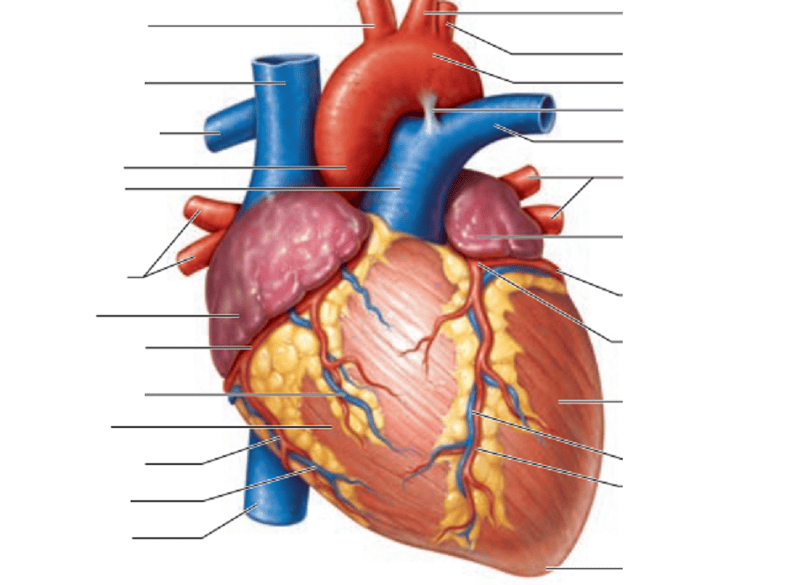

Name the missing parts.

Heart frontal section